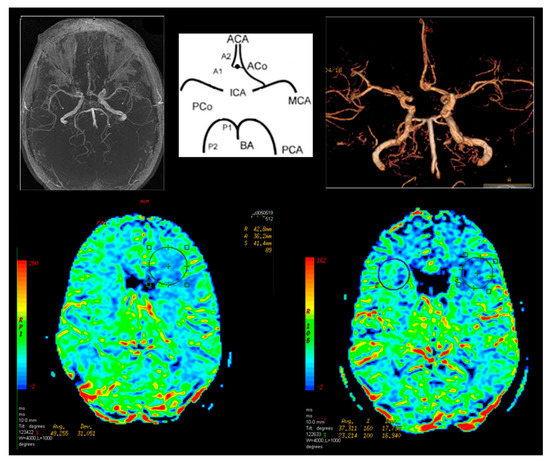

In Group I, 24 patients (60%) had abnormalities in cerebral perfusion parameters on P-MR without Acetazolamide. In 15 patients there was a reduction in perfusion in the hemisphere on the affected side. In PA-MR, perfusion disorders were found in all subjects. In 28 cases, they appeared on the affected side (Figure 4).

In Group II in one patient (6.6%), after the basic P-MR, perfusion disorders on the operated side were observed. In six cases (40%) with PA-MR the differences between the hemispheres were greater than 10%. They corresponded to the operated side.

Figure 4. Magnetic resonance brain perfusion with Acetazolamide and magnetic resonance angiography of the intracranial arteries. Right internal carotid artery—70%, left internal carotid artery—90% (operated side). Differences after admission of Acetazolamide marked with circles (right side).